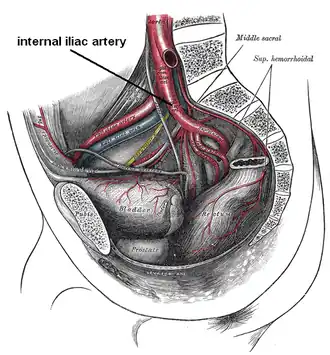

Male hypogastric artery

Male hypogastric artery -